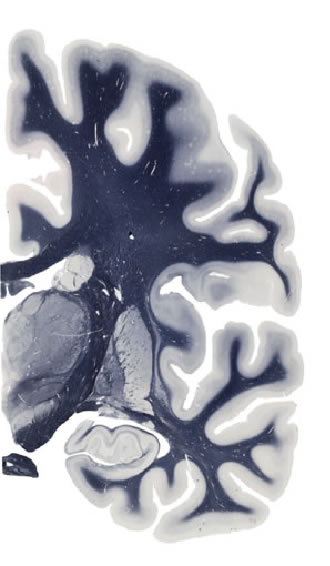

Hi-Resolution Sections · Cells (Nissl Staining) · Virtual Microscopy

Frontal sections (Nissl) from the Atlas Brain:

Slice ID:

r3-0803

Plate NR:

ca 34

Position:

16,0 mm